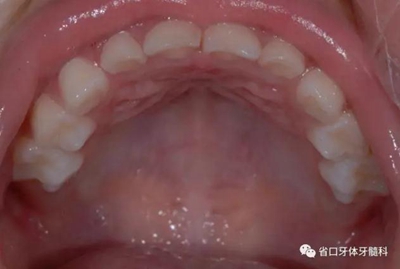

圖7 上頜牙相

8.jpg